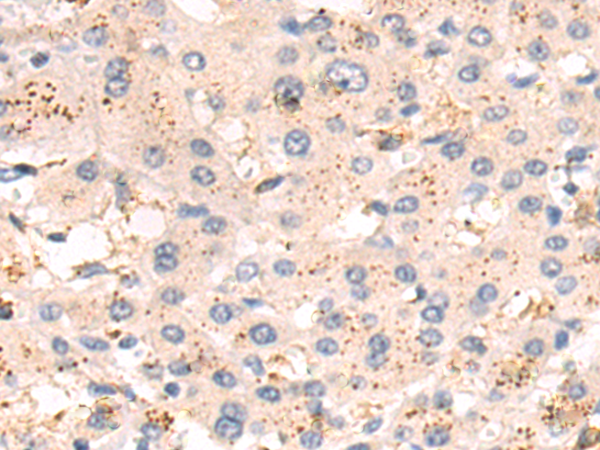

分类: 科研抗体货号: P10727别名: FAD, FACD, FAD1, GLM3, BRCC2, FANCB, FANCD, PNCA2, FANCD1, BROVCA2应用: IHC反应种属: Human